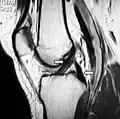

RMN-ul arată semnal normal al ambelor ligamente încrucișate (săgeți)